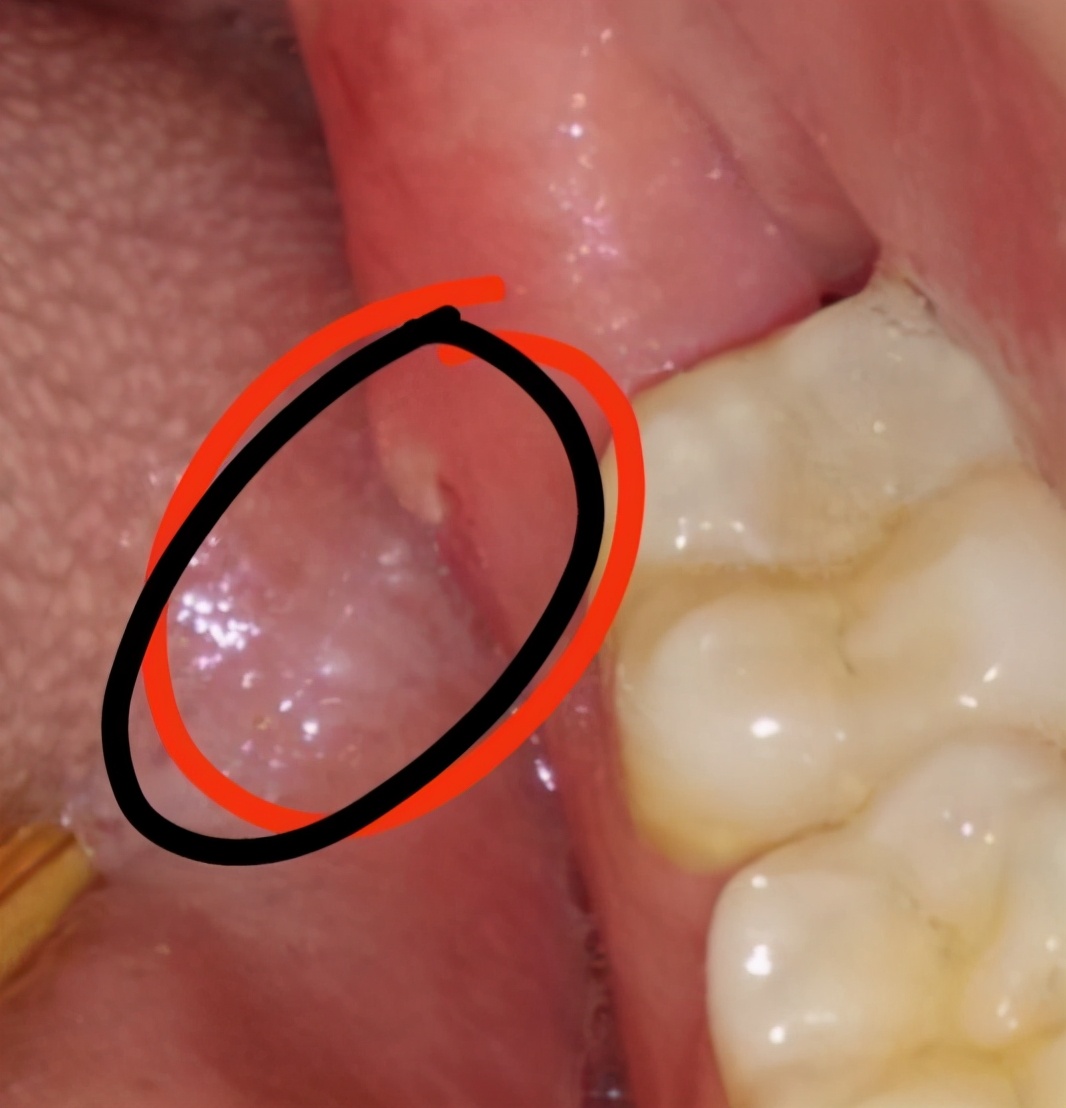

没错这就是我的牙齿!一个月前,右下方智齿萌出的位置发炎了,然后去口腔科拍了个片子,发现我有四颗智齿,上面的两颗都没有萌出,左下方的智齿也没有任何不适,建议先拔右下方的这颗!

6、智齿生长期间,可能会在智齿周围冒出小骨刺,我们可以在每天刷牙后用手按摩骨刺部位,促进骨刺吸收和消除,亲测有效!